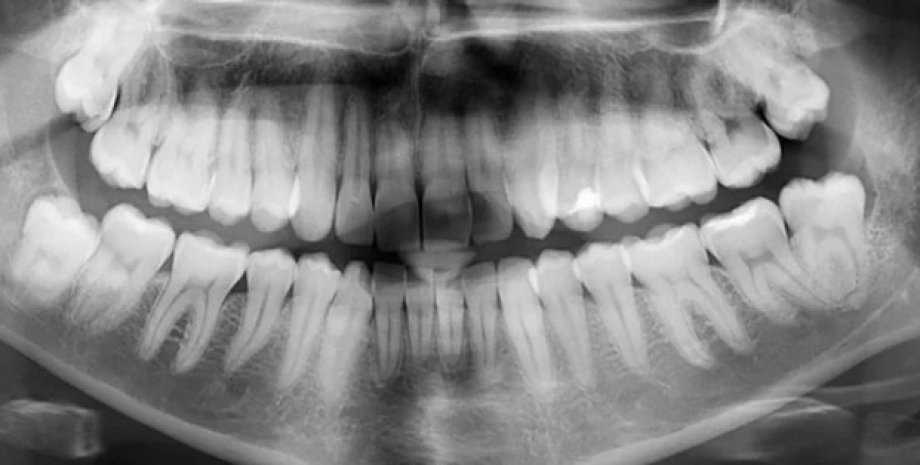

Фото: ScienceAlert | У 25% людей на Земле отсутствует хотя бы один зуб мудрости

Зубы мудрости представляют собой третий набор коренных зубов, расположенный в самой задней части человеческого рта. Они выглядят также, как и другие моляры, однако иногда могут быть меньшего размера, пишет IFLScience.

Эти зубы получили свое название из-за того, что появляются последними из 32 постоянных зубов, как правило, это происходит в возрасте от 17 до 25 лет, когда человек становится старше и мудрее. Однако известно, что далеко не у всех людей на планете появляются все четыре зуба мудрости — статистика свидетельствует о том, что четверть людей на Земле лишены хотя бы одного из этих зубов.